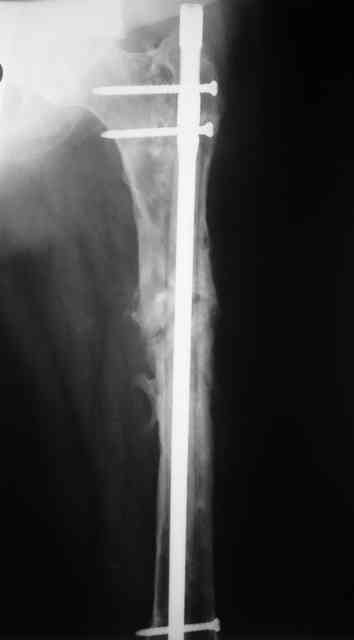

В настоящее время наш пациент ( см. http://weborto.net/forum/1177351385/) ходит с одним костылем. У него периодически открывается свищ на задне-наружной поверхности бедра с умеренным серозно-гнойным отделяемым. Температура тела и анализы нормальные. На рентгенограммах имеются признаки консолидации ложного сустава.

1, 2, 3, 4 - рентгенограммы бедра от 8 августа этого года (через четыре месяца после операции);